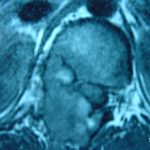

Εικ. 3: Μαγνητική τομογραφία α-στ Οβελιαία (Saggital) λήψη ακολουθία Τ1-Τ2, ζ-ιβ Εγκάρσια (Axial) λήψη ακολουθία Τ1-Τ2

Παρατηρείται ευμεγέθης εξεργασία στα οπίσθια στοιχεία του Θ12 σπονδύλου η οποία προκαλεί διόγκωση των δομών , λέπτυνση του φλοιού, χωρίς σημάδια διάσπασης του φλοιού. Η εξεργασία προβάλλει και στενεύει το σπονδυλικό σωλήνα, ενώ προκαλεί πίεση του νωτιαίου μυελού. Δεν αναγνωρίστηκαν παθολογικά ευρήματα από τον έλεγχο των σπονδυλικών σωμάτων και των μεσοσπονδύλιων τμημάτων της ΟΜΣΣ.